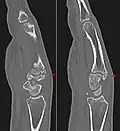

Carpometacarpal boss is uncommon and there is not much scientific data. Its etiology has yet to be fully defined, but can be congenital in the form of an accessory ossicle (os styloideum) or may be acquired from trauma, repetitive use, or degenerative osteophytosis.[3] The condition usually begins to show in the 3rd or 4th decade.

The joint between the index metacarpal and the capitate is a fibrous non-mobile joint. Some people have a gene that leads to this growth. It looks like arthritis (bone spurs on each side of the joint) on X-ray. It looks like a ganglion on the hand, but more towards the fingertips.